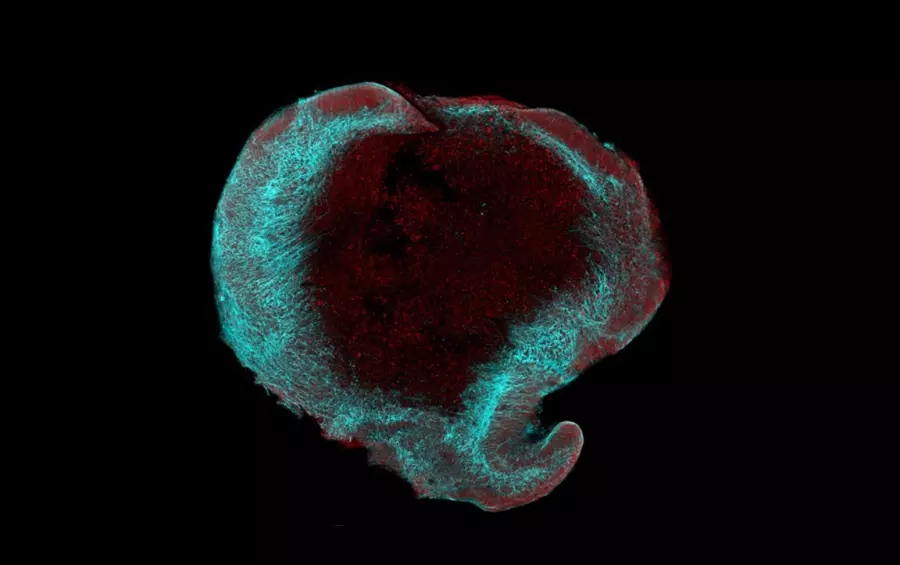

Mikroskopický snímek mozkového organoidu. Experimenty s laboratorně kultivovanými mozkovými organoidy prokázaly pozitivní efekt homotaurinu a dávají naději, že jsme blíže k léčbě Alzheimerovy demence. Ve světě se již vědci zabývají tím, jak využít vlastnosti homotaurinu v prevenci či léčbě kognitivních onemocnění a objev brněnských vědců nyní posouvá tyto snahy blíže ke klinické praxi.

Při experimentech vědci používali mozkové organoidy, což jsou „minimozečky“ vypěstované ve zkumavce z buněk pacientů s Alzheimerovou chorobou. „Mozkové organoidy jsme v této studii použili pro testování účinku homotaurinu na rozvoj Alzheimerovy demence. Naše výsledky potvrzují, že léčivo má pozitivní efekt na organoidy s variantou ApoE4, a ukazuje se, že ovlivňuje nejen důležité signalizační dráhy, ale také metabolismus cholesterolu. V dalších studiích se chceme zaměřit na podrobné mapování změn, které homotaurin v lidském mozku způsobuje,“ nastínila budoucí terapeutický efekt homotaurinu a další směr výzkumu buněčná bioložka Dáša Bohačiaková z Ústavu histologie a embryologie Lékařské fakulty MU.